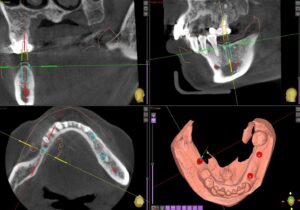

今回もコンピュータガイドを使って1本1本埋入位置を確認していきます。インプラントを埋める本数やデザインは最も好ましい条件から最低限の条件まで提示し、患者さんと相談の上進めていきます。今回は3本のインプラントを埋入しました。

ガイドを作成し、適切な位置に埋入します